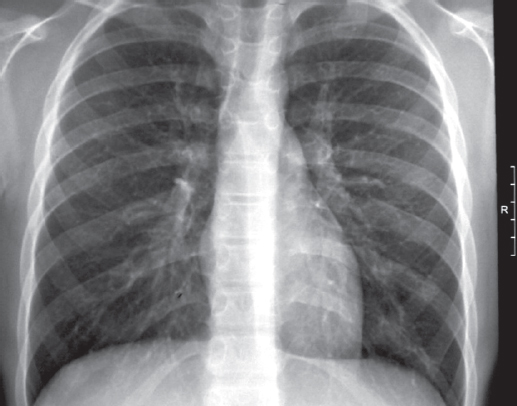

Поддерживающая терапия ОЛЛ проведена с 06.02.2013 по 19.08.2014 (назначены курсы метатрексата, дексаметазона), у ребенка констатирована стойкая ремиссия лейкоза. На фоне иммуносупрессивной терапии отмечались транзиторные изменения со стороны анализов крови (анемия, лейкопения, тромбоцитопения) от 12.03.2014: Er — 3,75 · 109/л, Hb — 105 г/л, Tr — 142 · 109/л, L — 2,9 · 109/л, п/я — 4 %, с/я — 41 %, мон. — 5 %, эоз. — 5 %, лимф. — 45 %, СОЭ — 16 мм/ч, с последующей нормализацией. В остальном состояние ребенка без патологических изменений. Курсы противотуберкулезной химиотерапии двумя препаратами (изониазид + пиразинамид и изониазид + ПАСК) проводили в периоды иммуносупрессивной терапии. Поддерживающая терапия ОЛЛ прекращена с 2015 г. Противорецидивное лечение туберкулеза продолжал в 2014 и 2015 гг. в летний период в санатории «Петродворец» (режим химиотерапии изониазид + пиразинамид). После 2016 г. курсов противотуберкулезной химиотерапии не получал, но контроль в противотуберкулезном диспансере был продолжен. Особенность контрольной иммунодиагностики туберкулеза состояла в следующем. В связи с медотводом гематолога с момента заболевания ОЛЛ в 2012–2014 гг. кожные иммунологические пробы не проводили. В 2013 и 2014 гг. проведен in vitro IGRA-тест — T-SPOT.TB, результат положительный. В 2015 г. проба Манту с 2 ТЕ: папула 17 мм, проба с аллергеном туберкулезным рекомбинантным — 20 мм. В связи с выраженной местной реакцией мать мальчика отказалась от дальнейшего проведения кожных проб. МСКТ органов грудной полости 2013, 2014, 2015 гг.: «Очаговых и инфильтративных изменений не выявлено. Изменения во всех группах внутригрудных лимфатических узлов стабильны, их размеры и степень кальцификации не нарастают». Последнее обследование в противотуберкулезном диспансере проведено в 2018 г. Ребенку было 12 лет, здоров. Туберкулезный контакт отсутствует (мать и тетя — клиническое излечение, дедушка переехал в другой регион). T-SPOT.TB — положительный. Обзорная рентгенограмма органов грудной полости — патологии не выявлено (рис. 4).

Рис. 4. Пациент, 12 лет. Обзорная рентгенограмма органов грудной клетки 16.08.2018 (6 лет наблюдения). Патологии не выявлено

Fig. 4. Patient, 12 years old. Plain X-ray of the chest organs 16.08.2018 (6 years of observation). No pathology was revealed

Клинический анализ крови — без патологии. Наблюдение в противотуберкулезном диспансере было завершено в 2018 г., в дальнейшем до настоящего времени наблюдается детской поликлиникой, здоров.